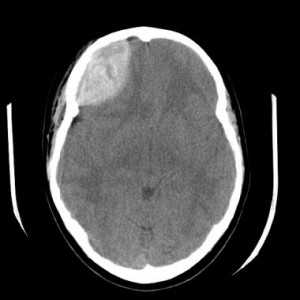

- КТ головного мозга. Как правило, на томограммах внутримозговая гематома имеет вид очага гомогенной плотности округлой или овальной формы. Если гематома сформировалась в результате ушиба головного мозга, то она обычно имеет неровный контур. С течением времени происходит уменьшение плотности гематомы до изоплотного состояния, при котором ее плотность соответствует плотности мозговой ткани. Для малых гематом этот период составляет 2-3 недели, а для средних — до 5 недель.

При КТ-исследованиях, сразу после кровоизлияния отмечается высокая плотность гематомы примерно до 80 ед. Н, что обусловлено структурой излившейся¸ неподвижной крови. Этот очаг обычно окружен различной по размерам зоной пониженной плотности. Вследствие распада гемоглобина, в сроки от нескольких дней до 2 недель плотность гематомы уменьшается, становясь идентичной плотности мозгового вещества (изоденсивная фаза). В это время КТ-диагностика геморрагий становится трудной.

КТ. Эпидуральная гематома.